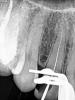

Magdalena Опубликовано 15 октября, 2012 Поделиться Опубликовано 15 октября, 2012 (изменено) Коллеги, кто сколько корней видит? Я вижу два.Или нет? Ход каналов практически не виден.Жалобы только на наличие кариозной полости, вскрыла - внутри тяж черной пульпы. Времени мало было, инструмент по доли мм (к-файл №8, 10) двигался. Изменено 15 октября, 2012 пользователем Magdalena Ссылка на комментарий

Magdalena Опубликовано 16 октября, 2012 Поделиться Опубликовано 16 октября, 2012 У тебя ведь скоп есть.Что в него видно? Кать, времени маловато было, скоп у меня перевозной, тяжелый, не успела в него посмотреть, не планировалось эндо. Но завтра, конечно, посмотрю. Если хода нет совсем, пломбировать на сколько пройду? Ссылка на комментарий

Magdalena Опубликовано 18 октября, 2012 Поделиться Опубликовано 18 октября, 2012 (изменено) Вот что получилось во второй раз Здесь верхушка была опилками забита, первоначально на всю длину прошла. Потом отмыла снова. Файл очень сильно изгибался на конце, начинала с №6.В первое посещение оставляла эдта жидкий в канале под витример.В итоге: корень один, канал один. Изменено 18 октября, 2012 пользователем Magdalena Ссылка на комментарий